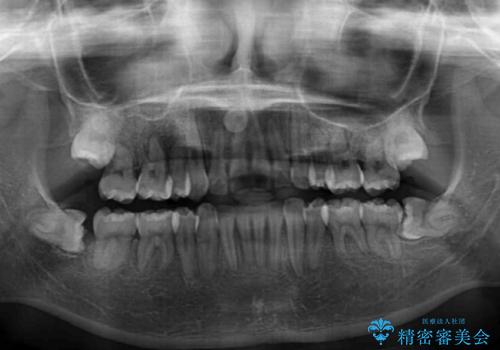

- 骨格的な咬み合わせのズレ、前歯のデコボコとクロスバイトを気にして来院された患者様です。

口元の突出感が若干あり口が閉じにくく、デコボコが強いため、上下左右の小臼歯計4歯を抜歯し、ワイヤー装置による矯正治療を行うこととしました。

また、舌の突出癖が強く、下顎前歯が前方に押し広げられる可能性が高いため、舌癖の改善を継続的に行うよう指示しました。

治療中に舌の突出癖が改善されず、下顎前歯が著しく前方に突出して反対咬合となってしまう局面がありました。

アンカースクリューを使用しながら舌癖の改善を図り、何とか咬み合わせを改善することができました。